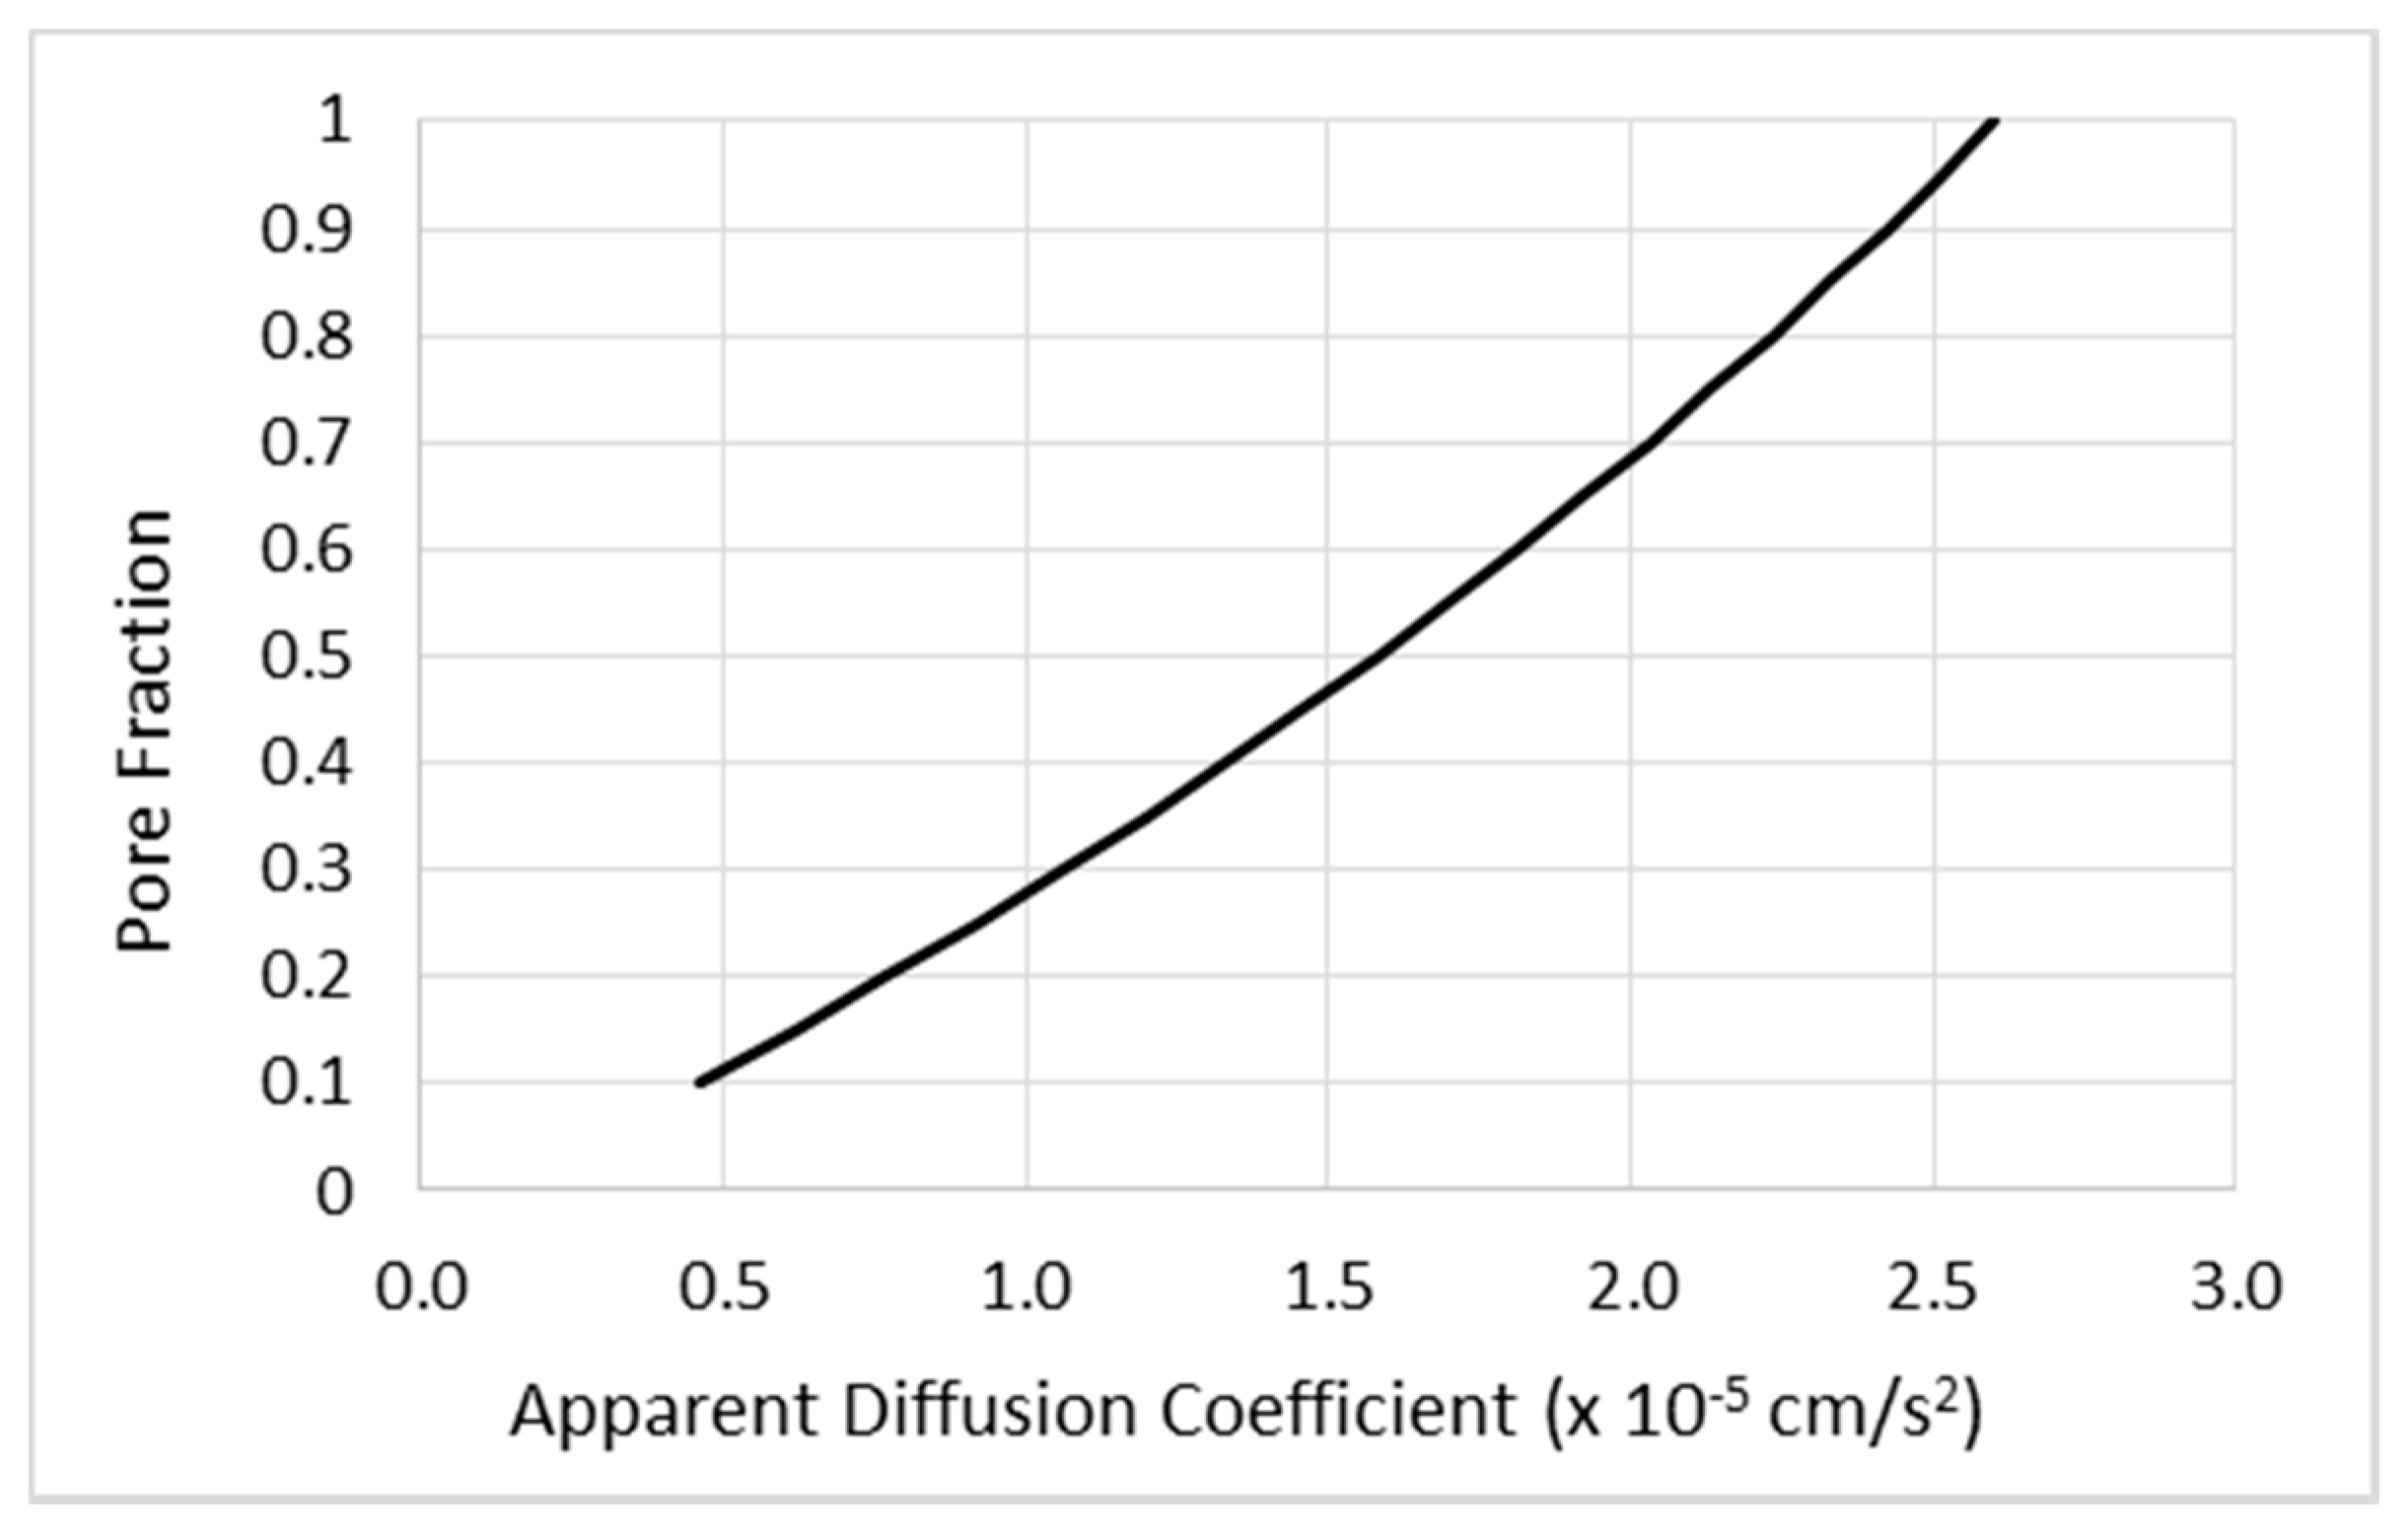

2.1. Simulation Models and Methods

2.1.1. Mathematical Modeling of CED

2.1.2. Simulation Methods